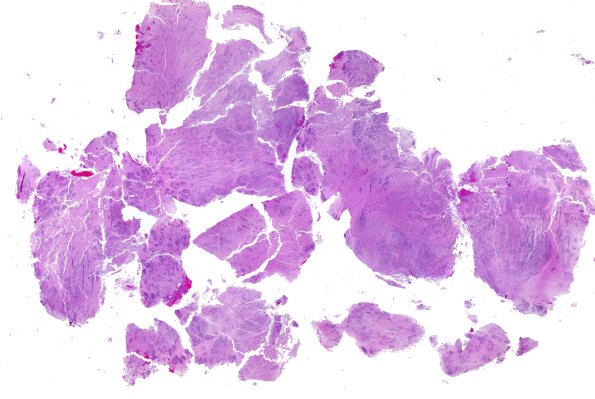

ETMR - Embryonal Tumor Multilayered Rosettes

8B1 ETMR (Case 8) H&E B1 WM

This low magnification whole mount shows a heterogenous pattern. (H&E)